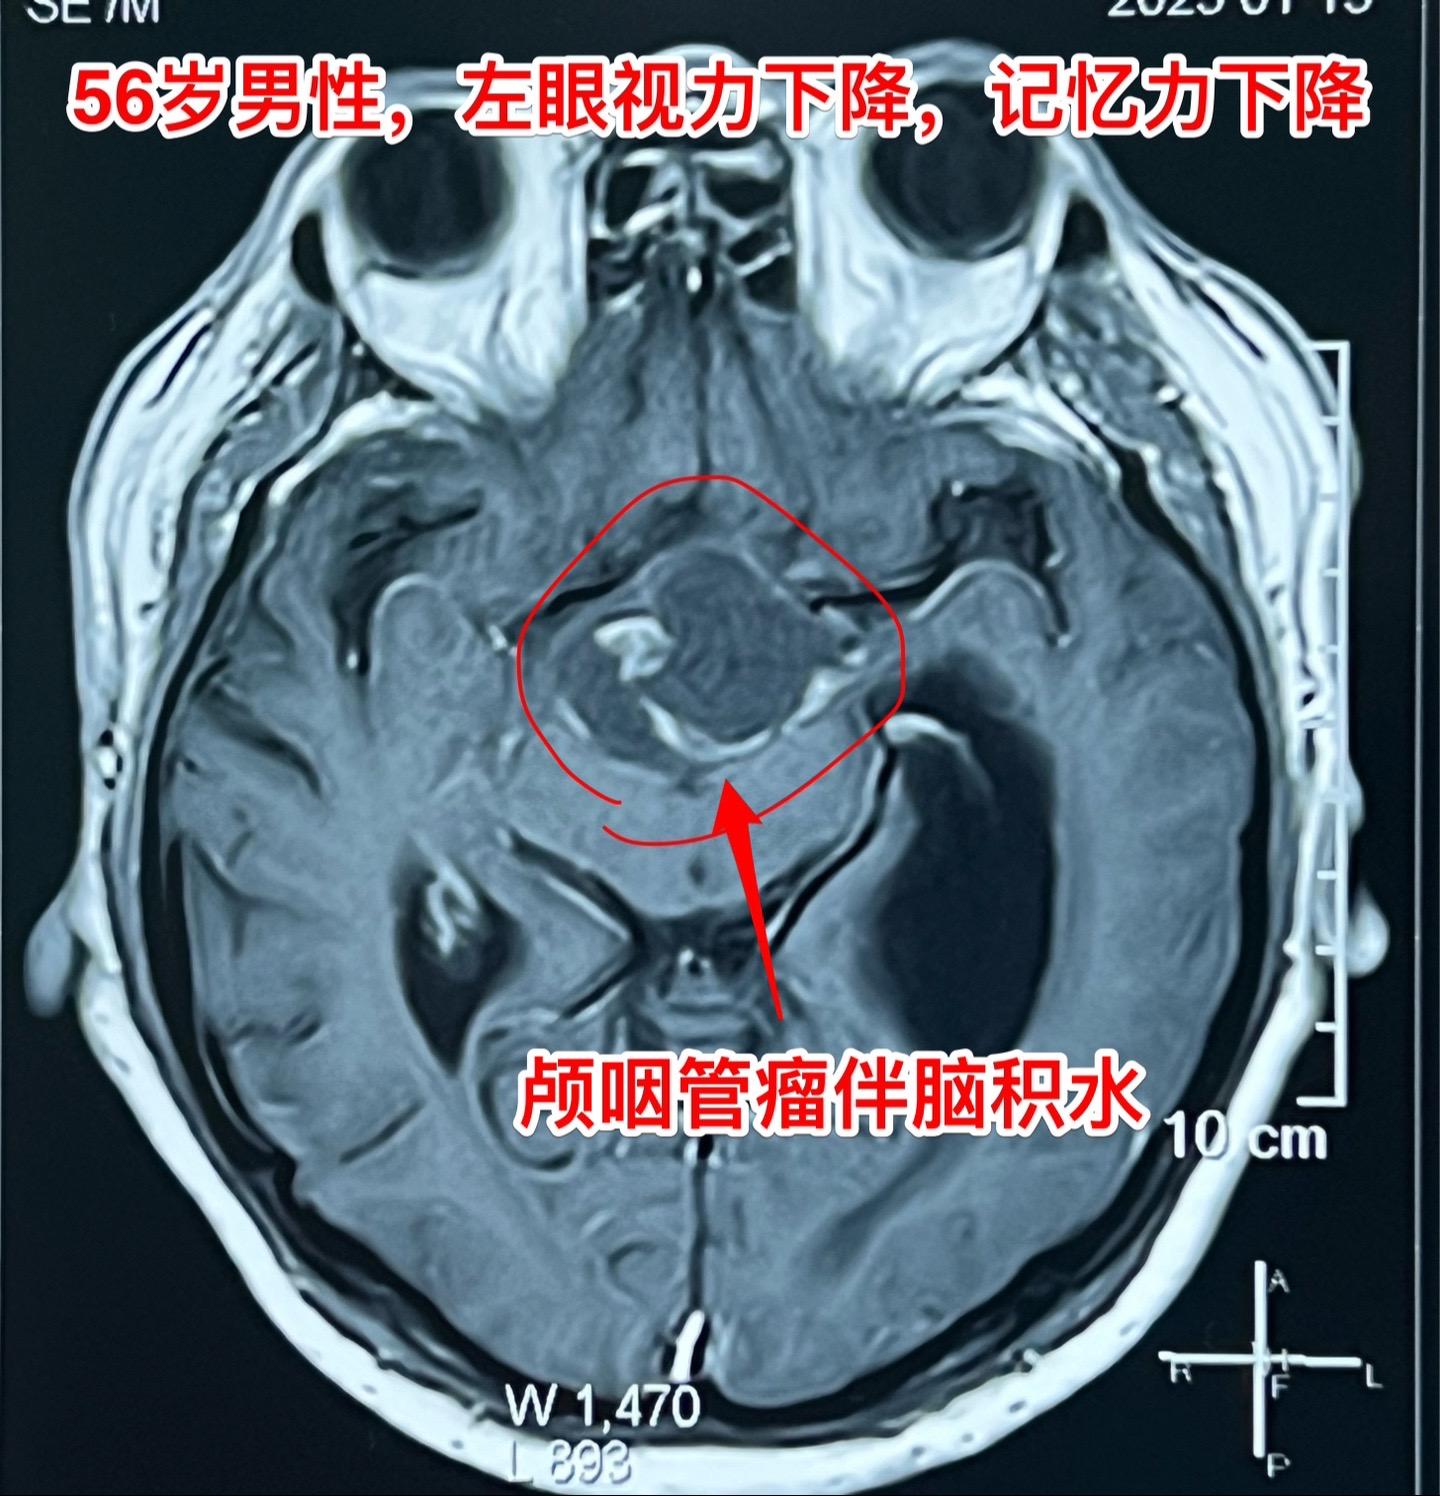

一天两个颅咽管瘤手术,凌晨两点才到家 科里年轻医生说还在关颅。 第一个病人广州人,56岁,左眼视力下降,检查出颅咽管瘤已经半年了,近期出现记忆力下降。病人之前一直在赶在过年前来作手术。今天的手术很顺利。 第二个病人是40岁大同市男性,思维糊涂、精神萎靡,坐轮椅到三博脑科医院就诊,颅咽管瘤伴有脑积水。今天的手术也是很顺利。